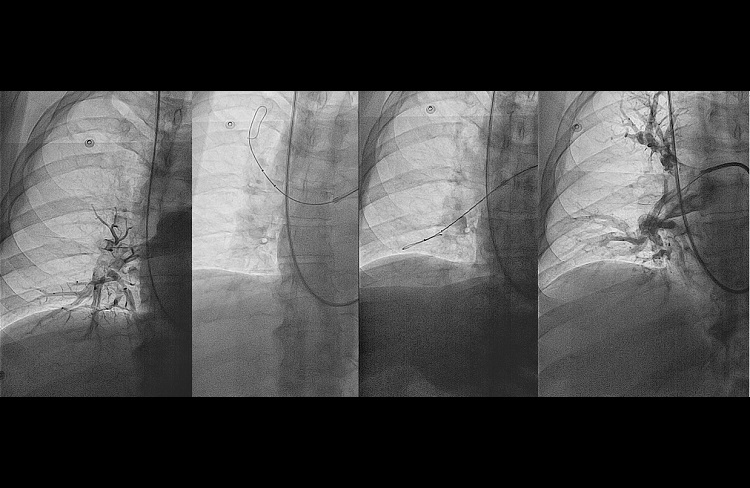

- diagnostyka ostrej zatorowości płucnej (angiografia tętnic płucnych);

- przezskórna embolektomia tętnic płucnych z wykorzystaniem nowoczesnego systemu do trombektomii mechaniczno-reolitycznej Angiojet oraz cewników do trombektomii apiracyjnej PENUMBRA Indigo;

- angioplastyki balonowe tętnic płucnych u chorych z nieoperacyjnym zakrzepowo zatorowym nadciśnieniem płucnym;

- Roik M, Wretowski D, Labyk A, Kostrubiec M, Irzyk K, Dzikowska-Diduch O, Lichodziejewska B, Ciurzynski M, Kurnicka K, Golebiowski M and Pruszczyk P. Refined balloon pulmonary angioplasty driven by combined assessment of intra-arterial anatomy and physiology–Multimodal approach to treated lesions in patients with non-operable distal chronic thromboembolic pulmonary hypertension–Technique, safety and efficacy of 50 consecutive angioplasties. Int J Cardiol. 2016;203:228-35.

- Rzadkim odległym powikłaniem ostrej zatorowości płucnej jest nadciśnienie płucne o etologii zakrzepowo zatorowej (chronic thromboembolic pulmonary hypertension, CTEPH). W Klinice prowadzimy pełną diagnostykę chorych z podejrzeniem CTEPH, a tod 2014 wykonujemy plastyki balonowe tętnic płucnych u chorych z potwierdzonym CTEPH nie zakwalifikowanych do leczenia kardiochirurgicznego. Zabiegi wykonywane są z zastosowaniem nowoczesnych metod wewnątrznaczyniowego obrazowania (FFR/IVUS/OCT) co zwiększa bezpieczeństwo i skuteczność tych zabiegów.

- Plastyki balonowe tętnic płucnych u chorych z potwierdzonym zakrzepowo zatorowym nadciśnieniem płucnym z zastosowaniem nowoczesnych metod wewnątrznaczyniowego obrazowania (FFR/IVUS/OCT), co zwiększa bezpieczeństwo i skuteczność tych zabiegów.